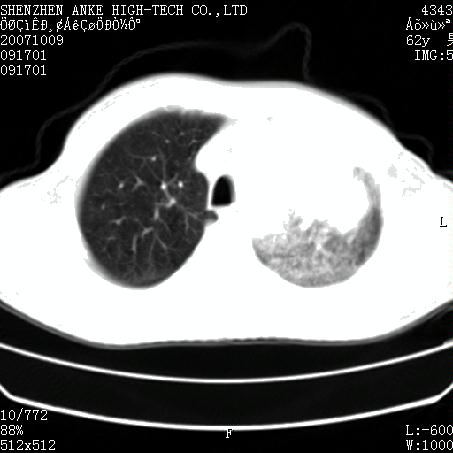

患者:男,62岁,咳嗽、胸痛、咯血约2月

左侧中央型肺癌伴上叶肺不张\\阻塞性肺炎.

左侧中央型肺癌伴上叶肺不张、阻塞性肺炎、纵隔淋巴结转移。支持!

左侧中央型肺癌伴上叶肺不张及阻塞性肺炎,纵隔内淋巴结转移